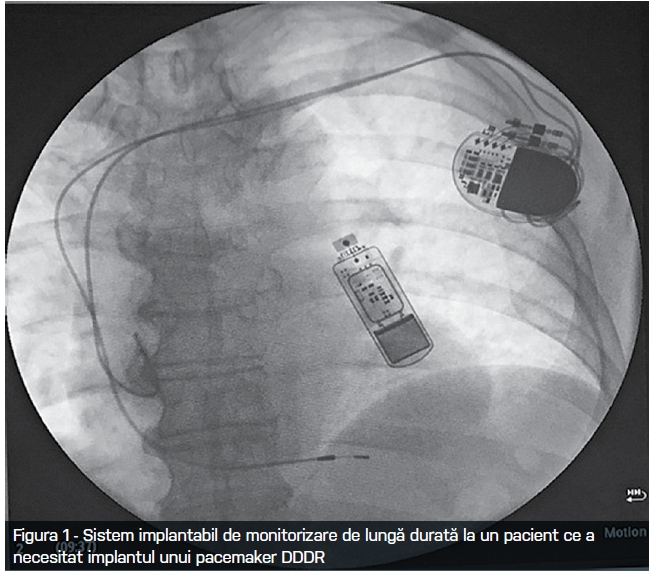

Pasul decisiv pentru monitorizarea continuă de lungă durată a fost făcut prin miniaturizarea sistemelor implantabile subcutan precordial. Acestea au devenit – precum stimulatoarele cardiace pe a căror platformă au fost inițial construite în anii 90 – prin miniaturizare și creșterea memoriei de înregistrare, din ce în ce mai des folosite. Astăzi, inclusiv la noi în țară, se trece de la sistemele de tip așa numite ILR ( implantable loop recorder) sau ICM ( implantable cardiac monitor) ce presupun o mică incizie precordială de sub 1 cm, la schimbarea către “insertable/injectable”cardiac monitor – care rezolvă orice “problemă” estetică legată de introducerea monitorului fiind introduse practic printr-un tip de injectare. Greutatea dispozitivului s-a redus de la 15 g la sub 3 g iar capacitatea acestora de înregistrare a electrocardiogramelor este de 3-4 ani!! Relevarea și utilizarea datelor înregistrate poate fi făcută atât la controalele periodice asemănătoare celor pentru pacemaker cât și automat, zilnic, prin preluarea automată cu ajutorul unui dispozitiv prezent la domiciliul pacientului și care interoghează wireless dispozitivul implantabil și trimite datele automat prin internet unui centru de control și medicului curant (monitorizare de la distanță = remote monitoring).